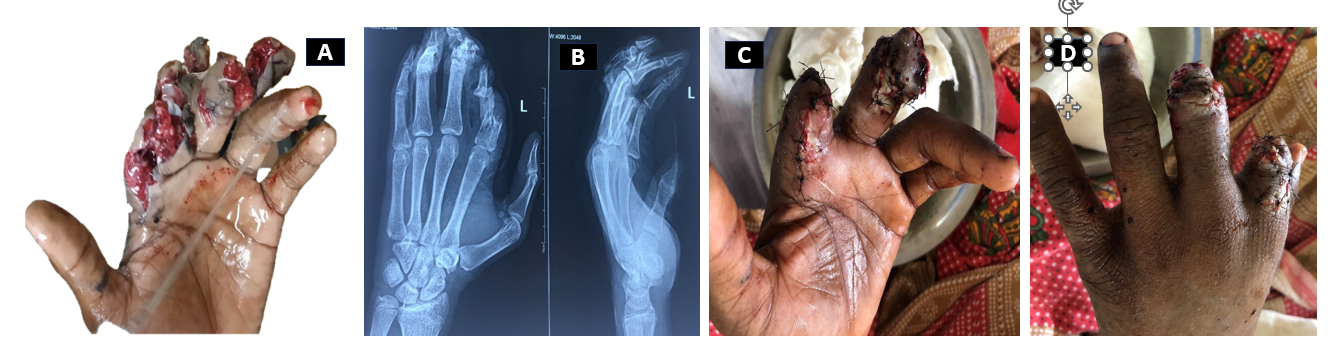

A few cases are illustrated in the Figs. 1, 2, 3, 4.

Figure 3: 25/M with Blast injury with multiple injuries (a). Immediate treatment: Wound debridement + Primary suturing (b and c) Soft tissue coverage – Groin flap (d), Flap detachment – Day 21 (e), Follow-up visit – at 3 months (f).

Figure 4: A 32 year male patient with crush injury following road traffic accidents involving multiple digits (a and b), X-ray – fracture middle phalanx of index finger (IF) and shaft of 5th metacarpal (MC) (c), Treatment: Wound debridement + open reduction internal fixation and K-wire fixation of IF + Miniplate screw fixation of 5th MC + local flap (cross finger flap cover) over raw area (IF) (d), Follow-up (1 month): K wire in situ + division of cross finger flap with follow-up (e-g).